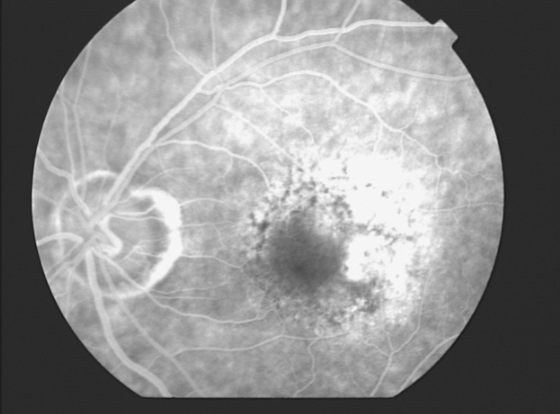

type 2 MNV

MNV is now b/t neurosensory retina & RPE making the IVFA more obvious & well defined

IVFA shows lacy, well-group area of neovascularization

hyperfluorescent early in study

late leakage

lacy early fill of the MNV during the choroidal & arterial filling phase

may have hypofluorescence corresponding to RPE hyperpigmentation & blood in the outline of the MNV

progressive hyperfluorescence throughout the FA w/o leakage of the margins of the MNV

type 2 MNV

MNV type 2

MNV type 2

MNV type 2

MNV type 2

MNV type 2